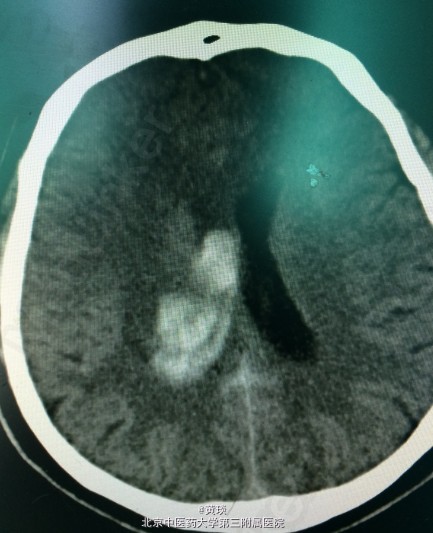

患者男,46岁,主诉:左侧肢体麻木伴进行性意识障碍5小时。 现病史:患者5小时前无明显诱因出现左侧肢体麻木,伴头痛,约4小时前出现呕吐,为喷射性,呕吐物为胃内容物,逐渐出现意识障碍,无肢体抽搐,约3小时前出现小便失禁,言语模糊。120送我院急诊就诊,行CT检查提示脑室内出血,于急诊给予保守治疗,患者意识障碍加重,预手术治疗收入院。

辅检:头CT示:右侧侧脑室内高密度影,脑室铸型(脑室铸型就是出血量过大,填满脑室,开起来就好像灌注雕塑一样)

初步诊断: 脑出血 脑室铸型 处理:颅内血肿清除术